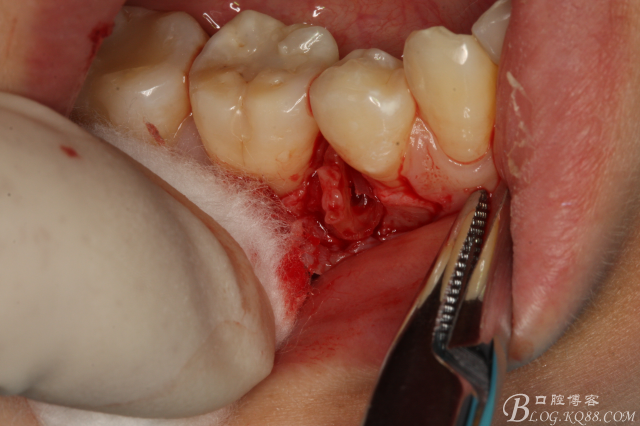

圖8.高速球鉆去骨約3mm.

圖9.暴露45頰側(cè)根面約1/2.牙根與44、46牙根緊緊相鄰。無法直接用挺。

圖10.高速裂鉆垂直分根